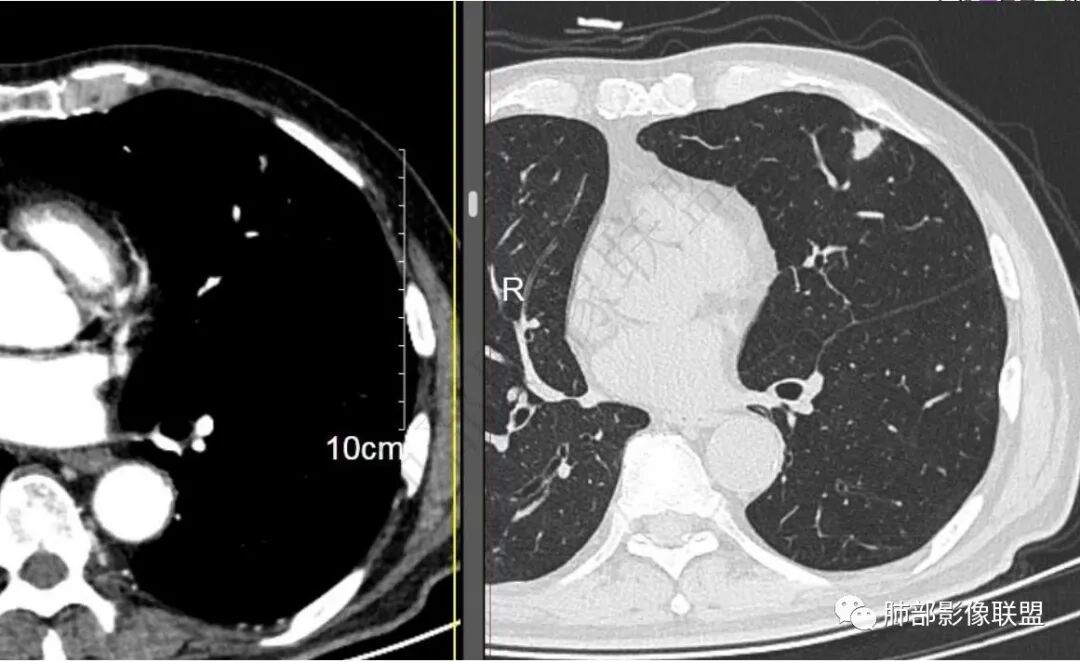

二..发现左肺上叶舌段实性密度小结节影,不规则略呈半环形,边界清楚,未见分叶、毛刺及磨玻璃晕。未见卫星病灶。

9个月后病灶明显增大,边缘较平直,部分膨隆,锁扣样外观,仍旧缺乏典型深分叶及张力,未见胸膜凹陷。

再1个多月后病灶继续增大,较明显不均匀强化,肺门一侧见低密度区。病灶边缘相对不清,可见毛刺。